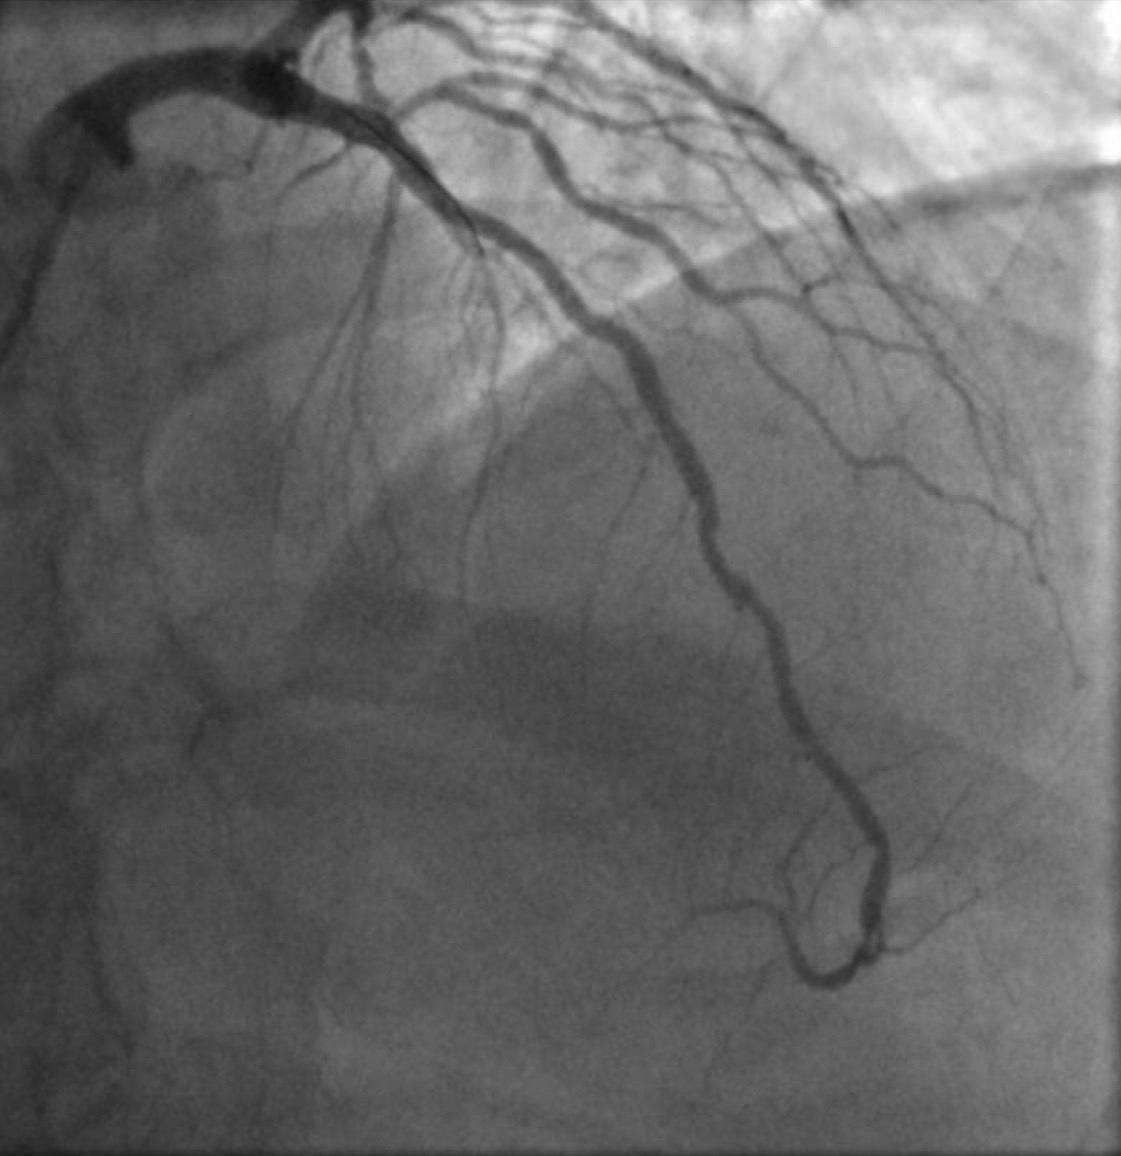

Almost 60 years later and all emergency roads lead from Troon to either Ayr or University Hospital Crosshouse, a couple of miles outside Kilmarnock, which opened in 1984 and in 2023, unfortunately, was brought to literary infamy by John Niven’s best-selling memoir O Brother. It dealt with the tragic death by suicide there of his brother Gary, from Irvine. I know, however, because my daughter has worked there and loved it, that Crosshouse is the place for me, suffering as I am from chest pain and all the panicky fears associated with a decade of living with a much-repaired and genetically dodgy heart. Ten years ago, it was a close thing. That Lateral Anterior Descending Artery had narrowed in several places to almost nothing. Like trying to squeeze the entire Clyde estuary through the Forth and Clyde Canal.

It’s a tribute to the Cath Lab (catheterisation laboratory) at Aberdeen Royal Infirmary (especially the bravery and skill of Dr Ryan), the Gilbert Bain Hospital in Lerwick, various GPs and other doctors, notably ones named Morton and Bowie that I’m still functioning today. Many nurses, paramedics, ambulance drivers, Scottish Air Ambulance pilots and porters, too. The full and glorious of panoply of care in Scotland’s NHS. Heartfelt thanks, always. Through technology and magic, arteries have been expanded by balloons and braced with mesh. Add a daily cocktail of medications and blood will flow. Has been flowing.